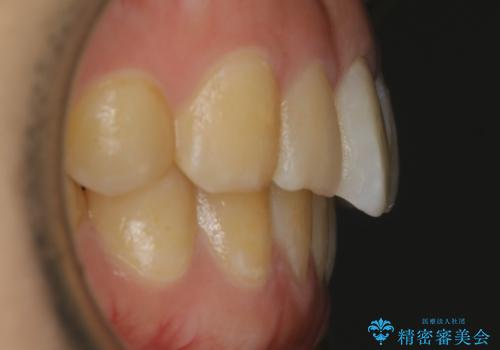

【非抜歯】ガタつきと歯軸を正して長持ちする歯へ

- 歯のガタつきと噛み合わせの改善を主訴に来院されました。

非抜歯で、少量の奥歯の移動と歯列の拡大・IPRを駆使して主訴を改善するための治療計画を立案しました。